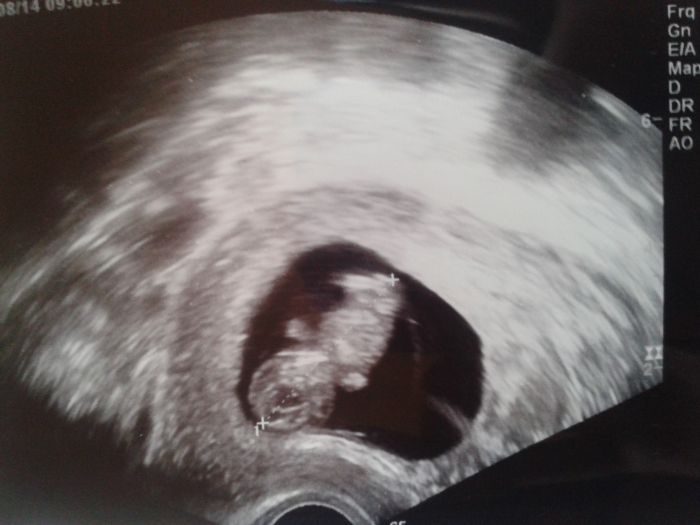

Tak se také hlasím po další kontrole. Prcek za měsíc krásně vyrostl jsem v 10+5, ale průkazku mi mudr nedala a dost mě vyděsila, protože prý ten otok co má za šíjí je moc velký 2,6 mm a že by u něj mohla být nějaká vada tak mi hned brali krev příští pátek jdu na genetiku a na konzultaci se specialistou ... kdyz jsem se jí ptala jestli je možnost že by se to mohlo spravit rekla ze mozny to je ale moc se netvarila vubec nevim co mam delat tak hezky se tam vrtelo a tohle me naprosto odrovnalo. Nechtela mi nic moc rikat at me nevydesi jeste vic ale vubec si nedovedu predstavit co budu delat vsechny varianty co mě napadlyjsou pro mě strasny ...

jsem z toho šokovaná vic ze to hned tak poznala z obyc ultrazvuku uz v 11 tydnu ale chodím do prenatalu a tam maji perfektni ultrazvuky, procitala jsem diskuze a pisou ze norma je do 3mm a ze do 14 tydne se to vytrati nebo pak uz se to nemeri tim ze plod vyroste ... doktorka mi rekne ze k tomu budeme pristupovat jako k normalnimu tehu ale prukazku mi neda tak co si o tom mam myslet potrebovala bych nekoho s kym to probrat ale v rodine jsme se to rozhodli tajit dokud nebudu presne vedet co bude ... rikam si ze to porad neni tolik a ze se to vytratit muze malý má 3.5 cm ke konci 11 tydne nezda se vam to malo? tak strasne se bojim

Ahoj mamky čekatelky. Tak se k vam po měsíci hlasim. Vítám tu nové maminky :) Začali me trápit vnější hemeroidy a zácpa, nikdy jsem problém neměla a dr mi tedy řekl že je to tou změnou a ze samo odezní, tak snad .. Jsem sice boubelka,ale poznám rozdil mezi spickem a tehu bříškem, jak se rika zacina se nam rýsovat podbřišek :) zvracet jsem přestala před 14 dny, bolest prsou mi taky dost ustoupila.tak jsem byla cela vyklepana co se děje a samozřejmě myslela na nejhorší. Ale pan doktor nás včera potěšil :) podle PM 11+4, a podle utz 10+1 :) na kombinovaný test jedu za 3 týdny do Ústí nad Orlicí, nebyla jste tam nektera uz ? Pojišťovna tohle nehradí, tak budeme dávat 1000 korun, ale určitě to za to stoji. Jinak mame 3,39 cm :) Pro pana doktora byl nadlidský ukol prcka vyfotit, hrozne tam sebou házel, :D ale nakonec se povedlo, tak přikládám fotku :)

jj nezoufam jen jak to tu ctu to asi nikdo jiny neresi ... a to se jeste obavam mam rh - tak aby nebyl porblem s krevni skupinou. ale nechci to vzdat ten mrnous uvnitr urcite taky bojuje. o tehotenstvi jsem v rodine rekla ale o tom co ten resime nic rikat nechci az budu vedet verdikt. kdyz se divam na foto toho ultrazvuku sleduju jen ten otok a nic jinyho je to strasny ... pritom kdyby mi to nerekla divny by mi to nepripadalo